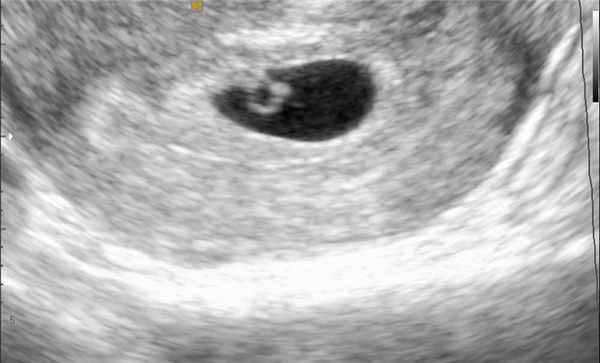

Если женщина, у которой ранее была подтверждена беременность, жалуется на боли внизу живота и/или в пояснице и кровянистые выделения из половых путей, то врач сразу подозревает, что у пациентки может быть выкидыш. Диагноз подтверждается на УЗИ: до 9-й недели беременности выполняется УЗИ матки и придатков, после 10-й недели - УЗИ плода.

Ультразвуковое сканирование органов женской репродуктивной системы для оценки формы и размеров, а также исключения патологии.

УЗИ и количественное измерение уровня бета-субъединицы ХГЧ (бета-ХГЧ)

Диагноз угрожающего, неизбежного, неполного или полного аборта, как правило, возможен на основании клинических критериев (см. таблицу Характерные симптомы и признаки самопроизвольного выкидыша Характерные симптомы и признаки самопроизвольного выкидыша ) и положительного теста на беременность.

Ультрасонографию и количественное измерение уровня бета-ХГЧ также выполняют, чтобы исключить эктопическую беременность и определить, остались ли продукты концепции в полости матки (т.е. произошел полный или неполный выкидыш). Однако результаты могут быть неоднозначными, особенно на ранних сроках.

Пропущенный выкидыш предполагают, если матка не увеличивается или если уровень beta -ХГЧ низок для данного срока гестации или не удваивается каждые 48–72 часа. Пропущенный выкидыш подтверждают следующие данные УЗИ:

Прекращение ранее выявляемой сердечной деятельности плода

Отсутствие сердечной деятельности плода при его длине > 7 мм

Отсутствие утолщения желточного мешка (по данным влагалищного УЗИ), когда средний размер мешка (среднее значение диаметров, измеренных в 3 ортогональных плоскостях) > 25 мм

Диагностика. Самым надежным способом диагностировать угрозу выкидыша считается УЗИ. Высокая вероятность самопроизвольного аборта подтверждается, если УЗИ показывает, что плацента начала отслаиваться, а плодное яйцо сплющилось.